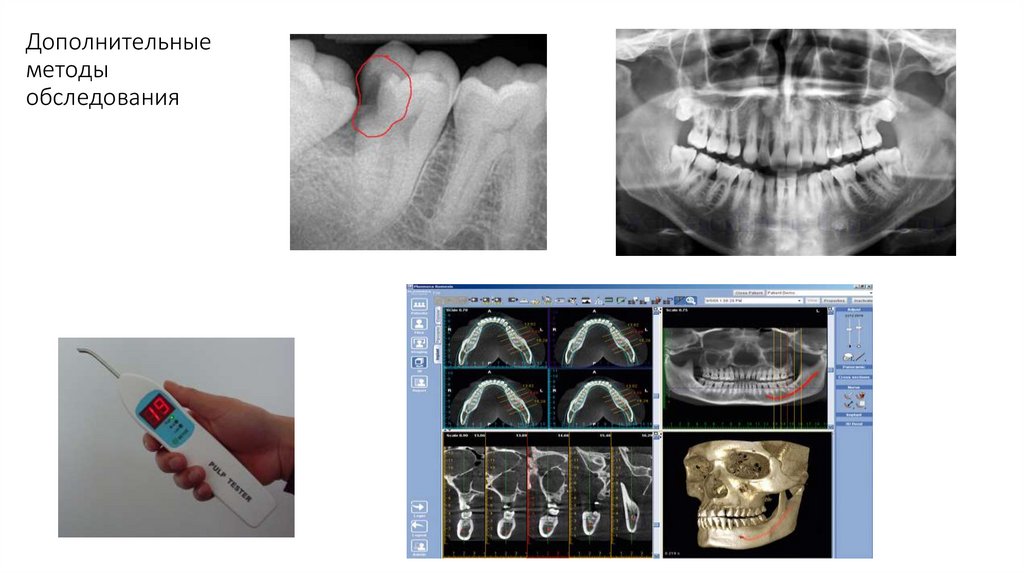

Дополнительные методы:

• рентгенологические,

• функциональные (электроодонтометрия, эстезиометрия, реография, полярография, зхоостеометрия и

др.),

• лабораторные (морфологические, бактериологические, иммунологические, клинический и

биохимический анализ крови, мочи и др).

• Рентгенологические: применяется внутри- и внеротовая рентгенография, панорамная

рентгенография, когда на пленке получают изображение обеих челюстей и всех зубов.

• Для уточнения локализации инородных тел, границ опухоли, при заболеваниях височнонижнечелюстного сустава используется послойная рентгенография- томография.

• При заболеваниях слюнных желез, хроническом остеомиелите челюстей, радикулярной кисте

применяют контрастную сиало- и фистулографию.

• В последние годы в диагностике патологических процессов челюстно-лицевой области значительное

распространение получили методы ультразвуковой диагностики и компьютерной томографии.

• Электроодонтометрия – измерение минимальной сила тока, на которую реагирует пульпа и ткани

периодонта.

• Реакция больного в норме возникает при воздействии электрическим током на здоровый зуб силой 26 мкА.